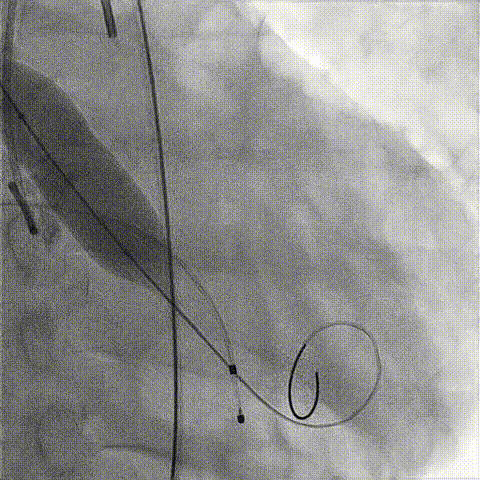

根部造影

球囊预扩

释放工作位造影

后扩后造影